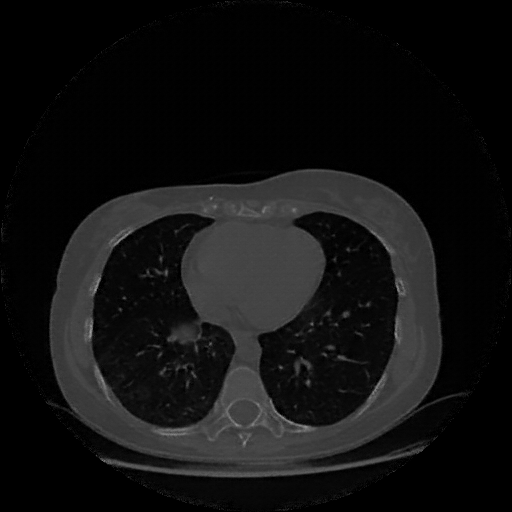

Original NATIVE CT scan (input)

Lung window (WL -600, WW 1500 β†’ Low βˆ’1350, High +150)

Reconstructed NATIVE CT scan (cycle consistency)